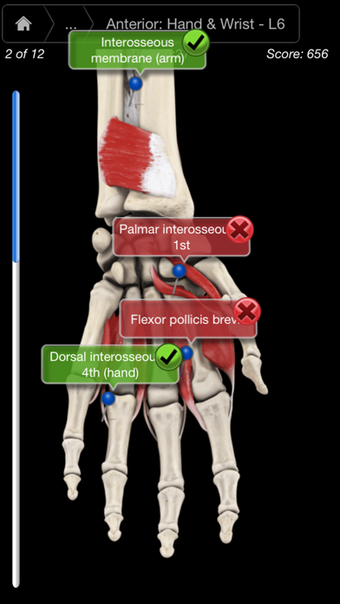

Muscle System Pro III - IPhoneเป็นโปรแกรมเวอร์ชันเต็มสำหรับ iPhone ซึ่งอยู่ในหมวดหมู่ 'ยา'

เกี่ยวกับ Muscle System Pro III - IPhone สำหรับ iPhone

Muscle System Pro III - IPhone พร้อมใช้งานสำหรับ iOS 12.1.2 ขึ้นไป เวอร์ชันปัจจุบันของโปรแกรมคือ 3.8.2 และคุณสามารถเรียกใช้ได้ในภาษาอังกฤษเท่านั้น